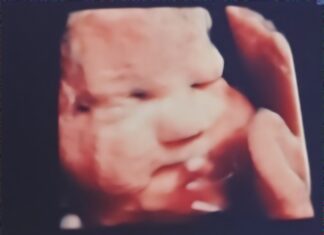

Local mother travels to Texas to seek care for unborn baby

CULLMAN, Ala. – Cullman resident Holliann Letson was enjoying a typical pregnancy with her second daughter, Evelyn. At her 18-week anatomy scan – the scan often referred to as the “gender scan,” as most...